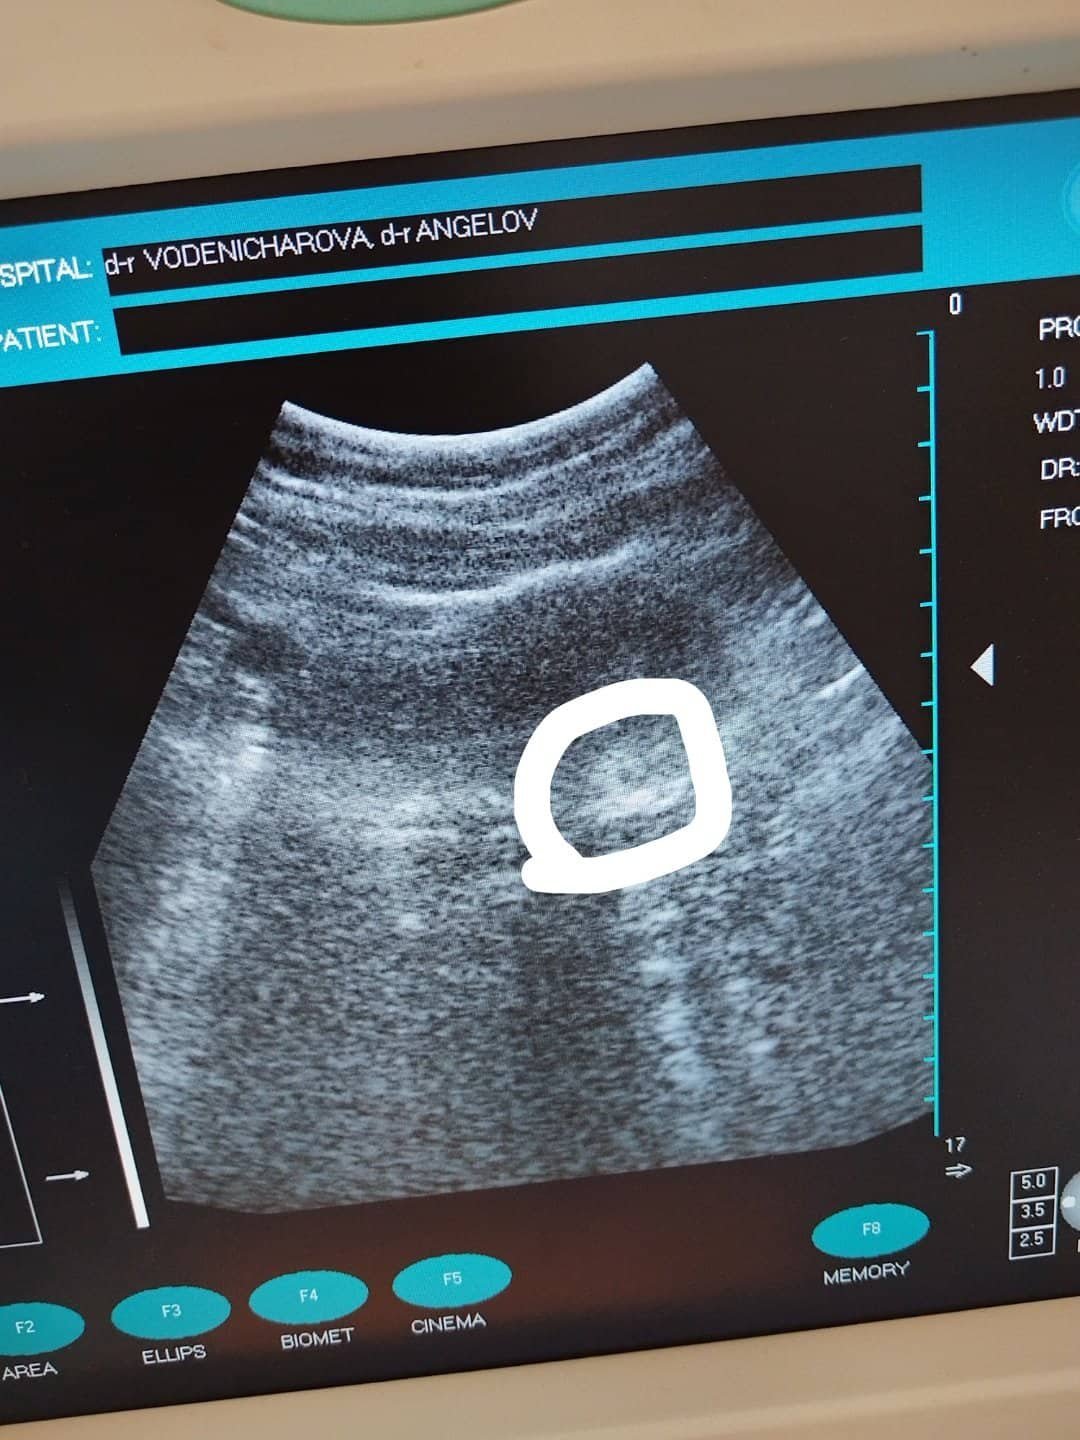

Биохимичната бременност е състояние, при което бременността започва, но не успява да се развие до етап, който може да бъде визуализиран чрез ултразвук. Това може да доведе до спонтанен аборт или леко кървене. В случай на биохимична бременност стойностите на ЧХГ обикновено не се увеличават както трябва и понякога дори намаляват. Важно е да се консултирате с лекар за допълнителни изследвания и наблюдение. Биохимичната бременност е форма на ранна загуба на бременността, която се характеризира с краткотрайна бременност, обикновено открита чрез кръвни тестове за хормони. Той се различава от нормалната бременност по това, че обикновено води до преждевременно или ранно спонтанно прекратяване. Биохимичната бременност е краткотрайна бременност, характеризираща се със значително ниски нива на хормона ЧХГ и обикновено водеща до преждевременно прекратяване на бременността. Биохимичната бременност е ранна форма на спонтанен аборт, която се случва преди да може да бъде открита с ултразвук. Тя обикновено се характеризира с временен скок в нивата на човешки хормон гонадотропин (hCG) и може да доведе до леко кървене или по-ранен цикъл. Биохимичната бременност е, когато бременността се потвърждава чрез ЧХГ и ултразвук, но не се вижда плодното сакче. Препоръчително е да изчакате 1-2 нормални цикъла, за да балансирате хормоните преди нов опит за бременност. Биохимичната бременност е успешна имплантация на яйцеклетка, но изходът от бременността е кратък, често завършващ с менструация, преди жената да разбере, че е бременна. Симптомите включват слаб положителен тест за бременност или кървене, което не е типично за менструация. Човешкият хормон гонадотропин (hCG) може да се измерва, но стойностите му обикновено започват да намаляват. Тези случаи обикновено не изискват медицински интервенции. Биохимичната бременност е ранна загуба на бременност, която обикновено се случва преди 5-та седмица. Обикновено при биохимична бременност тестовете за бременност дават положителни резултати, тъй като нивата на hCG се повишават, след което бързо намаляват и бременността не продължава.

Извънматкова бременност възниква, когато оплоденото яйце се имплантира извън матката, обикновено в една от фалопиевите тръби. Симптомите могат да включват едностранна коремна болка, вагинално кървене и дискомфорт по време на уриниране или дефекация. При извънматкова бременност нивата на ЧХГ може да не се повишат както обикновено или дори да намалеят. Това е сериозно състояние, което изисква незабавно медицинско внимание, така че е важно да се консултират с лекар при съмнение за извънматкова бременност. Извънматковата бременност е състоянние, при което оплоденото яйцеклетка се имплантира извън матката, обикновено в една от фалопиевите тръби. Симптомите включват коремна болка, кървене и нерведен менструален цикъл. Това е спешно медицинско състояние, което изисква незабавно лечение. Извънматковата бременност е състоянние, при което оплоденото яйце се имплантира извън матката, обикновено в една от фалопиевите тръби. Симптомите включват коремна болка, вагинално кървене и нисък ЧХГ може да бъде показателен за това състояние. Това може да доведе до тежки медицински усложнения и изисква спешно лечение. Симптомите включват коремна болка, вагинално кървене и нива на ЧХГ под очакваните за дадената седмица на бременността.